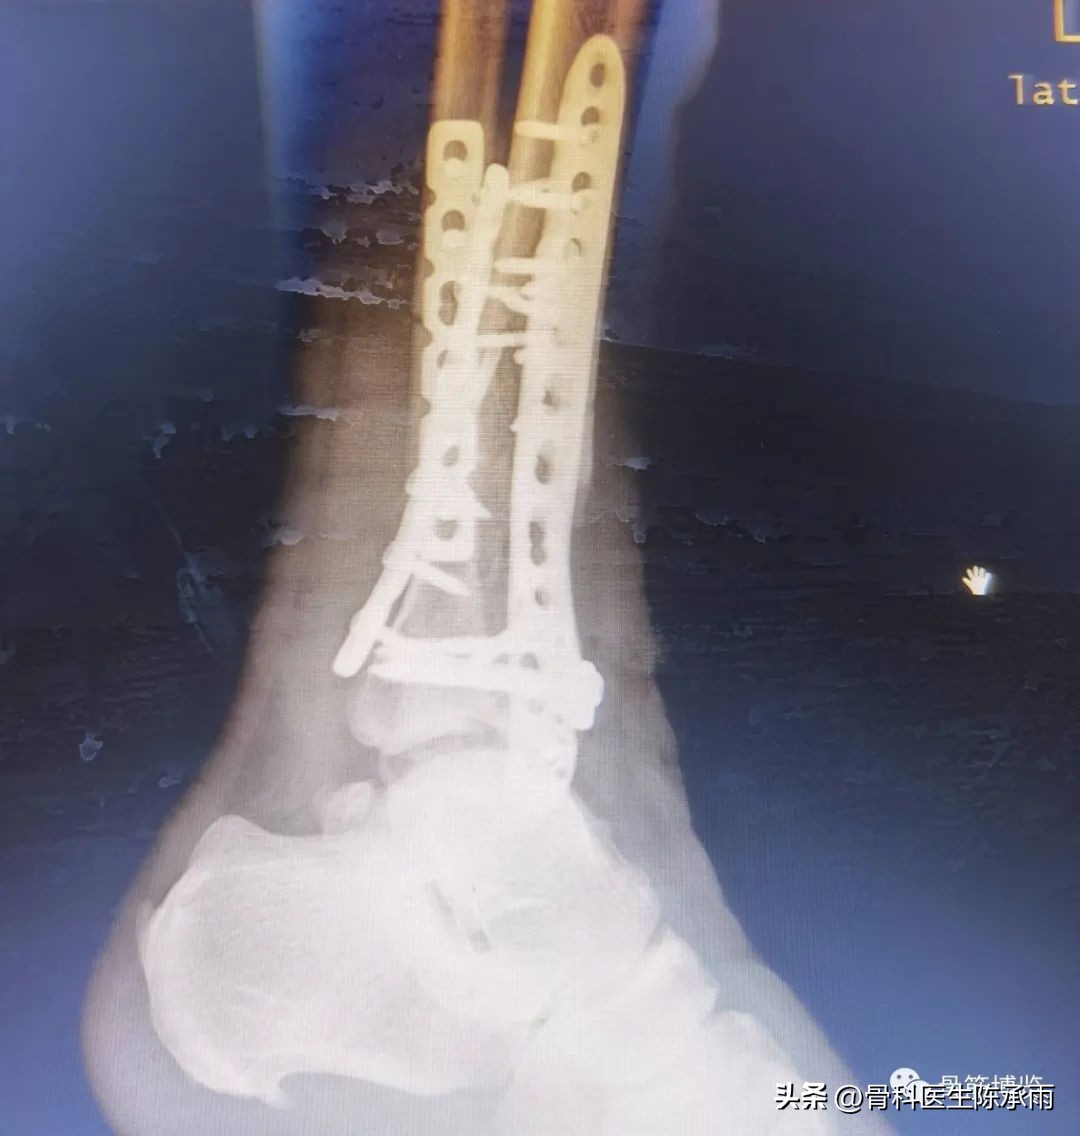

近日的1例股前外侧皮瓣修复查踝前皮肤缺损。